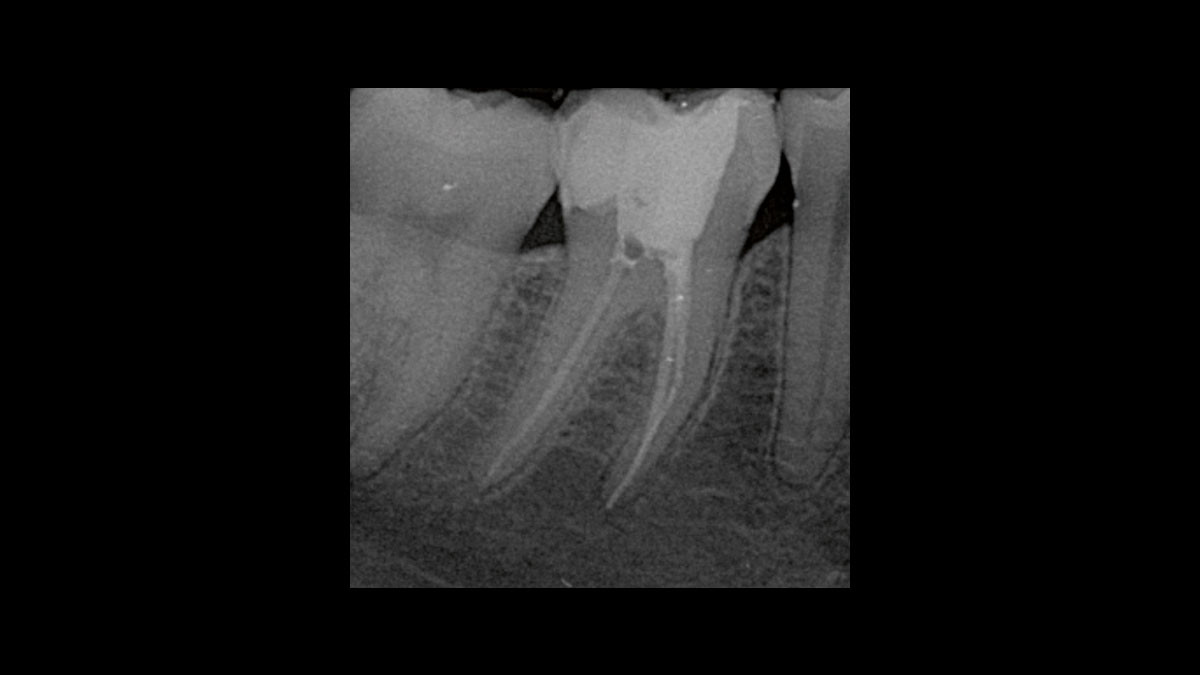

Endodontische Keimreduzierung